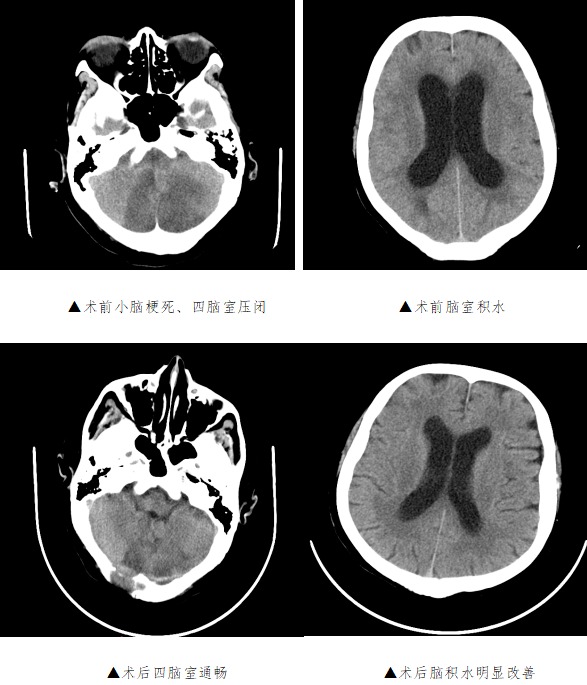

【医讯速览·新闻】第44期:小脑梗死陷入昏迷 神外术后清醒出院